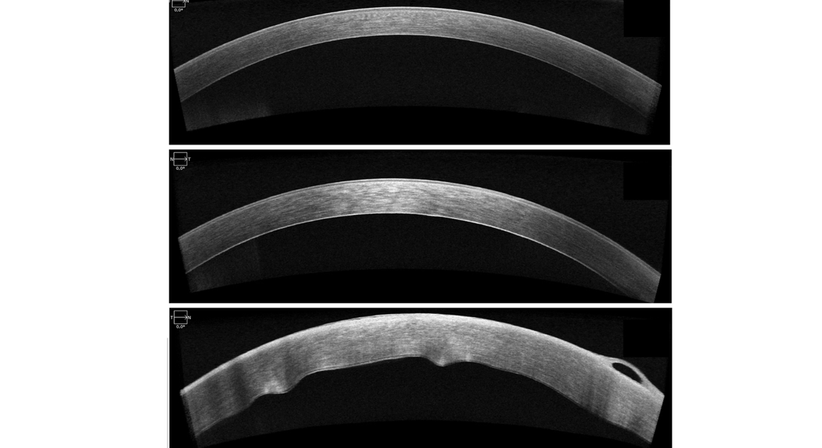

Hornhautnarben oder Unregelmäßigkeiten können ergänzend zur mikroskopischen Beurteilung am besten mittels hochauflösenden Laser-Schichtbildaufnahme (sog. OCT, optische Kohärenz Tomographie) untersucht und beurteilt werden. Auch dieses Messverfahren steht Ihnen in unserer Ordination zur Verfügung.